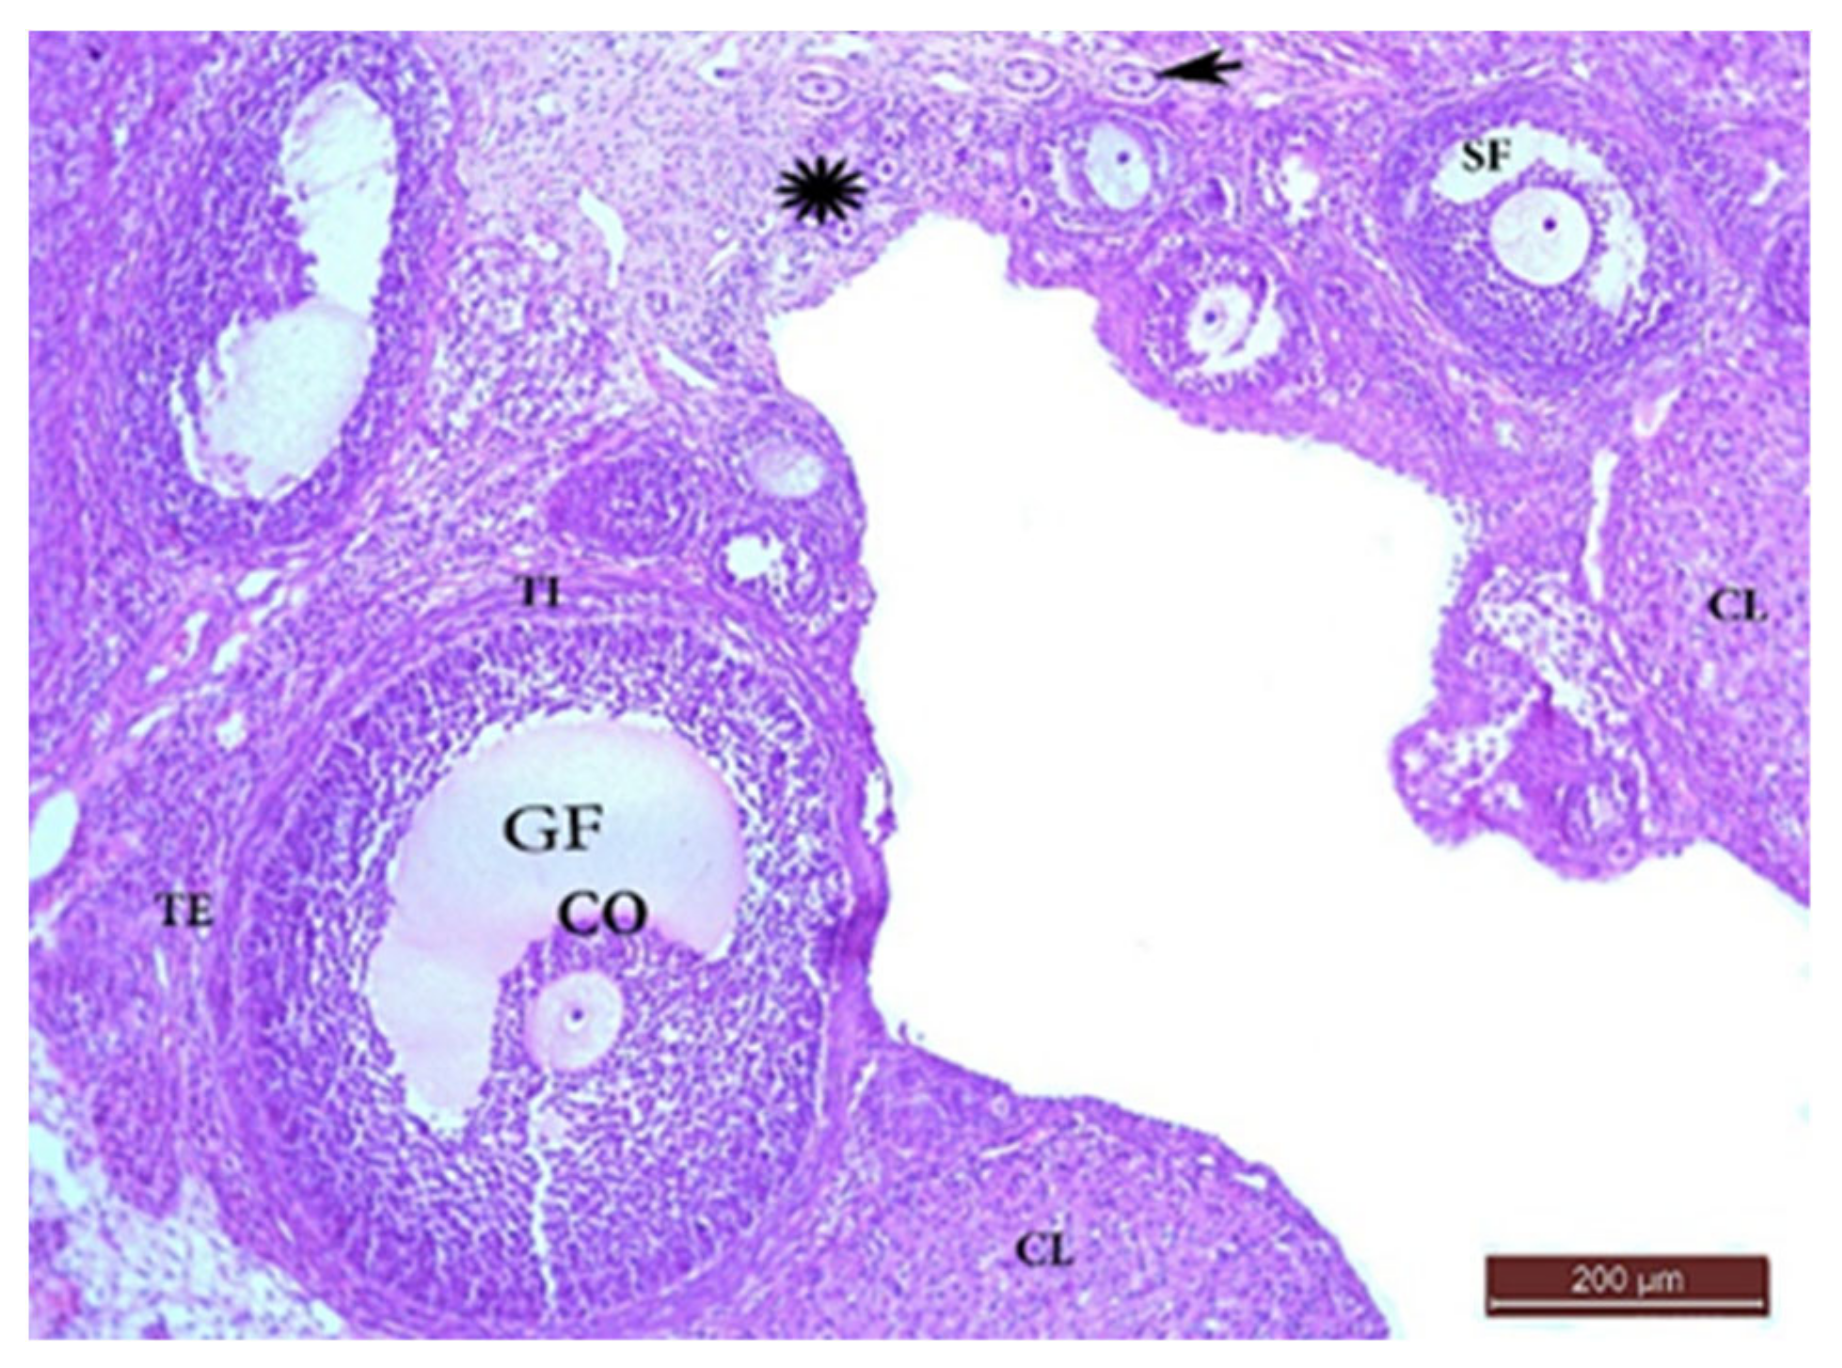

The Control Group (Group I, Figure 1, Figure 2, Figure 3 and Figure 4)